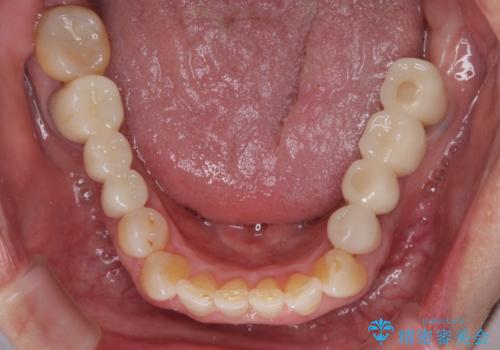

欠損の多い奥歯 インプラントによる補綴治療

右下の銀歯も気になるとのことで、インプラント治療と並行してオールセラミックによるブリッジ補綴治療も行うこととしました。

地元に戻られる前に無事に治療を終えることができました。

今後は東京出張のタイミングでメインテナンスに通院していただきながら、インプラントの状態をチェックしていくことになります。